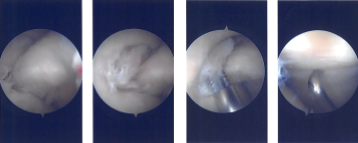

Intraoperative Arthroscopy Images

The patient was taken to the operating room where she was placed on a well-padded operating table. General anesthesia was induced. Low tourniquet was applied. IV antibiotics were given, before the tourniquet. A lateral entry portal was made. Arthroscope was entered into the patellofemoral joint and then into the medial compartment.

Then, the arthroscope was moved to the lateral compartment where a tear was seen. A medial entry portal was made with direct access to the left meniscus. The instruments were entered and the lateral margin of the medial meniscus, the fraying on the lateral margin of the medial meniscus was cleaned using a shaver.

The arthroscope was entered into the intercondylar area where there was partial tearing of the ACL fibers. The arthroscope was entered into the lateral femoral compartment where the tear was again seen. The third tear was thoroughly debrided using a shaver and straight bitter.

After the thorough debridement of the tear, the scope was moved into a patellofemoral joint where grade 3 to grade 4 osteoarthritic changes were seen. Chondroplasty of the posterior patellar surface was performed using a shaver.

There was grade 1 osteoarthritic change in the trochlea. was grade 1 to 2 osteoarthritic changes in the medial femoral compartment, medial femoral condyle posteriorly, which was shaved.

Now, the arthroscope was entered into the medial working portal and instruments were entered from the lateral portal. Final debridement of the lateral meniscus was performed. The knee was thoroughly irrigated and lavaged.

Final pictures were taken and saved. The scope was removed, and the knee was closed using #3-0 nylon. The 80 mg of Depo-Medrol and 18 mL of 0.5% Naropin was injected into the knee.